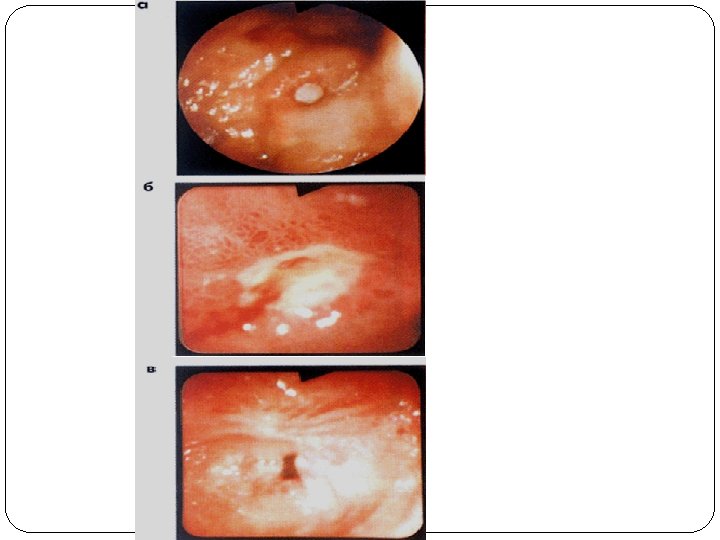

Malignization

malignant [neoplastic] transformation